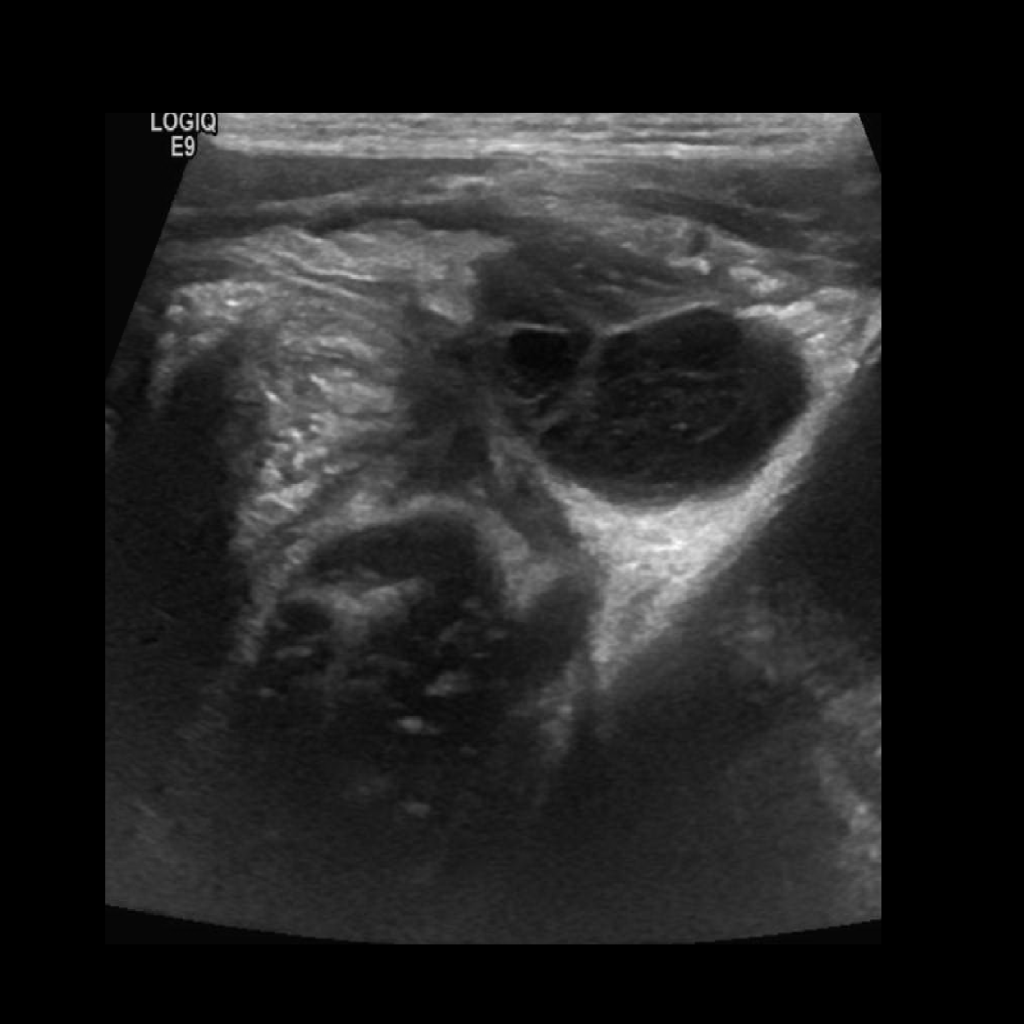

Appendicitis 9

Perforated appendicitis with complex collection/abscess formation, fat stranding and appendiolith.